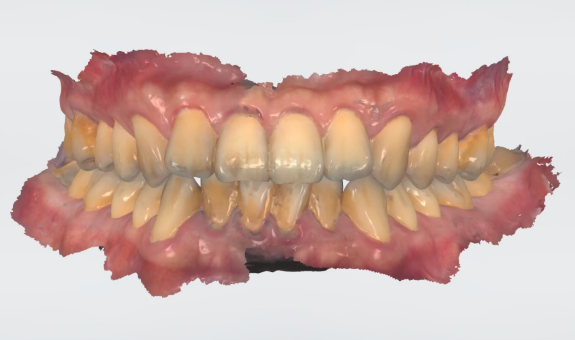

數位植牙的好處? 不管採取何種植牙治療方式,「4D微創導航系統」牙科技術能夠輔助醫師,在治療時,除了能透過醫師臨床的經驗與技術外,更能精準的控制與判斷病患的所有狀況,降低療程時可能發生的風險,以及減緩術後的不適感。 醫師會在病人的缺牙上,裝上一顆如同「監視器」的機器,搭配「4D動態導航系統」牙科技術,讓醫師在植牙的時候,能夠即時、精準的監測病人口腔骨頭內的狀況。 植牙有黃金治療時間嗎? 植牙的黃金治療期是「越來越快好!」為什麼是「越快越好呢?」最主要是因為牙齒與牙槽骨是相互依存的關係,當缺牙的第一年,骨頭會吸收得特別快,接下來每年以等比的速度吸收。 當口腔內的牙齒,有任何問題或是已經出現缺牙的情況,應該盡快尋求牙醫師的協助!進行治療與骨頭重建的需求評估,已避免增加重建的困難度,甚至無法治療。 到底適合「植牙」,還是要做利用兩邊牙齒做「牙橋」,最終還是需要經過醫師的專業判斷。 如何在茫茫醫海中,尋找適合的植牙醫師? 「一般牙科、贋復補綴科、口腔顎面外科、牙周專科」現代人很喜歡上網做功課,但想要找植牙醫師時,卻不知道從何尋找到適合的植牙醫師。 其實,能夠提供患者專業植牙技術的醫師,通常會受過「贋復補綴科、口腔顎面外科、牙周病科」這3大科的專業訓練。 擔心花錢後植牙出現問題又無法處理,如果長期看診的牙醫診所沒有相關的專業醫師,可以請醫師幫忙轉介。 另外,也可以挑選幾位自己喜歡的醫師,進行面診諮詢,找出最適合的醫師。最後,與醫師充分的溝通、配合也是植牙成功與否的重要關鍵。 植牙的步驟 植牙的流程大致可以分為幾個階段:資料蒐集、資料分析與重建理想牙位、植牙手術與植牙臨時假牙製作,以及最後最重要的植牙假牙製作。 植牙諮詢的第一步「資料蒐集」 資料蒐集、分析: 先利用口腔掃描機、臉部掃描儀、X光片、斷層掃描等,蒐集病患口腔整體環境、牙齦、骨頭的臨床資訊,以及紀錄顳顎關節與咬合的情況。 植牙手術 植牙手術:在經過專業的醫療團隊,進行術前評估後,以及擬定個人化的治療方針後,就會進入植牙手術的步驟,手術的步驟,會先進行牙齦翻瓣、鑽孔、植入人工牙根、縫合、拆線等。 不少人聽到上述步驟,或許已經頭皮發麻,專業的醫療團隊在治療的過程中,會搭配「舒眠麻醉」治療,能夠降低病患在過程中的不適感與恐聚感。 而通常人工牙根的癒合期大約需要6-12週的癒合,待癒合後才會進入「植牙臨時假牙製作」的製作。 植牙永久有效? 植牙有保固期 ? 「植牙成功後,就一勞永逸了嗎?就不用與醫師相見了嗎?」植牙它是鈦金屬釘子,植入骨頭癒合後,它不會蛀牙。但是,植牙周圍的牙肉跟骨頭,如果不妥善保養的話,還是會導致牙周病的發生,就是所謂的植體周圍炎。 植牙上方接出的牙冠,就好比買一台車,牙冠用久了,就如同車子用久了,零件、螺絲依舊會出現損毀的狀況,所以定期的回診保養追蹤是相當重要的。 通常植牙牙套完成後,至少半年回診一次,讓牙醫師檢查確認植牙附近牙齒沒有累積牙箘斑牙結石、植體周圍牙肉沒有發炎化膿,中間固定的螺絲沒有鬆動、牙套沒有破損、咬合狀況穩定等。 此外,患者必須維持良好的口腔清潔,可以參照之前我介紹的牙齒清潔方式,來保持好的口腔衛生、少抽菸等,如此搭配定期的回診檢查,可延長植體壽命。 植體的構造 植牙的治療過程很漫長,很多病患最常問的是「嘴巴內裝上的到底是什麼東西?」 今天的「植牙芯教室」就要帶你來認識「植牙整體的構造」(Dental implant) 口腔內的植牙由上→下依序是:牙冠、支台體、植體。 牙冠:又稱假牙冠、牙套,它是提供如同真牙的咀嚼功能,並且恢復美觀,永久性的牙冠最常見的材質為:全瓷、金屬合金、瓷熔合金屬。 支台齒:連接牙冠與植體的延伸部分,在中間點扮演重要角色,因為它必須要支撐牙冠的咬力,同時又要提供牙肉健康的生長環境,所以專科醫師在安裝時,必須依造病患口腔的狀況「客製化」的設計,ˊ尋找最適合的形狀、大小與角度。 植體:置入於缺牙的牙槽骨中,功能是取代原有的「牙根」,負責穩固牙齒的地基,目前最常見的植體材質為純鈦、鈦合金。 植牙x牙冠材質 對於越來越講求美觀的現代人來說,花錢植牙,當然希望它能美觀性與功能性兼具。 今天的「植牙芯教室」就要帶你來認識「牙冠材質」 目前,市面上永久性的牙冠最常見的材質為全瓷、金屬合金、瓷融合金屬 。 1.全瓷牙冠:材料有氧化鋯、強化玻璃瓷,不需要使用金屬,材質與人體的生物相容性高,同時具備高硬度的特性、高耐磨、耐高溫。在外觀上,呈色自然如同真牙,美觀性極佳。 2.瓷融合金屬牙冠:由於合金的成分複雜,若是高貴金屬的成分(黃金、白金)不夠高時,在口腔高溫潮溼的環境下,金屬容易腐蝕,導致表面粗糙,使牙菌斑難以徹底清潔,就容易造成牙齦發炎,並且染色,長期在美觀上、實用性都難以符合,對於外觀講求自然的病患。 3.金屬合金牙冠:由於整體採用金屬製作,所以不容易破裂、折斷,但是外觀呈現金屬色,所以當張開口時,便能夠一眼看出假牙的位置,如果使用金屬和金的牙冠,建議使用高貴金屬成分較高的材質。 植牙前的注意事項 想要提高植牙治療成功率,醫師與病患互相配合很重要,從術前的資料蒐集、評估與診斷,依據病人的情況,給予專屬的治療方針,從術中的治療過程,到術後的維護都非常重要,先來談談植牙前要注意那些事情。 1.保持口腔衛生:口腔清潔是植牙成功的最大關鍵 2.降低煙癮:抽菸會影響植牙的成功率,應該要盡量避免,如果能夠戒菸成功,更能提高植牙的成功率。 3.持續服用慢性病藥物:如果有在服用慢性病(高血壓、糖尿病等),在術前的諮詢,務必完整提供用藥歷史給醫師。 植牙後的潔牙步驟-工具篇 「植牙疏於潔牙與保健,百萬台幣立刻船過水無痕。」這是血淋淋的案例,真的不要以為,植牙完成後就一勞永逸。 術後的口腔清潔與維護非常重要!非常重要!非常重要!因為植牙的「使用壽命」,有非常大的關聯性。 植牙維護有三寶:牙刷、牙間刷、牙線 牙刷:可以選擇自己習慣的刷頭,或者選擇刷頭短小、刷毛軟硬適中的牙刷 牙間刷:當牙齦萎縮、牙縫變大時,應該選擇適合牙縫大小的牙間刷,用來清潔齒間的縫隙、牙套底層的牙菌斑與食物殘渣。 牙線:使用超級牙線,來清潔牙橋下的支柱牙部分。 漱口水、沖牙機等,這些只是輔助工具,千萬不能把它當作正規的潔牙器材。 植牙後的潔牙步驟-清潔篇 植牙的清潔方式。 首先:使用牙刷在假牙與牙肉的交界,採用刷牙法,來回輕刷至少10次。 接著:使用牙間刷,輕貼牙齒的表面,進行前後清洗,按照同一個方式,從舌側進入,輕貼牙齒表面,再做一次清潔,每次動作至少5次。 最後:使用大約45CM的牙線,可以使用穿引器的輔助,深入牙橋底下做清潔,每次動作至少5次。 植牙後的潔牙步驟-電動牙刷VS.一般牙刷 「做完牙套後可以用電動牙刷刷牙嗎?潔牙工具怎麼選?」上一篇,談了植牙的清潔方式,究竟植牙到底該不該用電動牙刷?答案是「可以」。 科學研究指出,使用電動牙刷,能更深入清潔到牙縫與牙齒倒凹處,尤其對於手部協調性沒那麼高的人,以及牙齒排列凌亂者,在清潔上能夠達到更好的效果。 刷頭的選擇:一樣要以刷頭小、刷毛軟硬度適中的刷頭,建議每1-3個月,或者外觀出現彎曲變形,刷頭就必須更換。千萬不要因為刷頭,比一般牙刷貴捨不得更換,反而會讓潔牙效果打折扣。 潔牙方式:電動牙刷與一般牙刷的潔牙方式的差異在於,電動牙刷只需要將刷頭輕放在單顆牙齒上,讓刷頭在牙齒與牙肉的交界處轉動,手不需要來回移動刷頭。但是千萬不要重壓,施壓過多的力道在牙齒上,反而對於牙齦是種傷害。 另外,不管使用電動牙刷或一般牙刷,都一定要使用牙線、牙間刷,來清潔牙齒與牙齒間的鄰接面,確保牙菌斑被清除。 潔牙時間:三餐飯後,30分鐘內如果能夠潔牙是最好的,如果無法達到,睡前徹底的潔牙是最重要!另外,潔牙時一定要有耐性,不要為了節省時間,隨便刷2.3下就結束。 如何選擇:預算、操作與攜帶方便度為首要考量,而且選擇具有「經濟部標準檢驗局」檢驗合格的產品,設計不良的電動牙刷,可能會造成口腔受傷。 植牙後的術後照護 植牙的最終成功與否,術後照顧真的非常重要!務必遵從醫囑,以下是照護的重點。 1.冰敷:術後1周,依舊會有些許的腫脹與輕微的瘀青,在48小時內,建議患者可以冰敷,在臉頰外側冰敷15-20分鐘,休息10分鐘,重覆動作到48小時。 2.不要泡溫泉、熱水澡,以及從事游泳與劇烈的運動。 3.飲食方面:初期還是會建議以流質、軟度高的食物為主,過燙、過冰的流質食物則不宜,應該避免食用過燙、辛辣、含有酒精成分刺激性的食物。 4.降低菸癮:為了讓植牙的傷口能順利恢復,醫學上皆有文獻記載,術後1周必須降低菸癮。 5.定期回診:植牙完成還是必須定期回診,讓醫師確認傷口、口腔健康的情形。 根據手術療程的不同,每一項術後的照護方式也有所差異,未來會跟大家分享與討論。 植牙後就能一勞永逸,不會有牙周病? 大多數的病患都知道,植牙前要先把牙周病及其他口內問題處理好,以降低口內細菌數量,才能夠進行植牙,但是很多病患以為,植牙成功,同時也能跟牙周病永久說再見,這觀念完全不正確。 簡單說「牙周病」是牙齒的周圍骨頭受到細菌的破壞,所造成的結果。因此,在植牙後,如果植體周遭的牙肉與骨頭,沒有得到妥善的清潔與照顧,還是會造成口腔內細菌的滋生,一樣會導致牙周病的發生。 植牙後,是不是也跟敏感性牙齒Say Bye Bye 一般所說的「敏感性牙齒」真正的學名是「牙本質知覺敏感症(Dentin Hypersensitivity)」會造成敏感性牙齒,主要原因是在於牙齒外層的琺瑯質被磨耗後,失去保護的功能; 或是牙齦萎縮牙根裸露時,都會造成牙本質內的神經小管暴露,當受到冷熱、吹氣、和壓力等刺激下,所產生的神經疼痛不適感。 植牙後,重建的人工牙冠內沒有神經,所以不會有敏感性牙齒的發生。然而,其他的自然牙齒,不會因為植牙而受到改變,當琺瑯質被破壞時,依舊會造成牙齒敏感性的問題。 骨質疏鬆的人適合植牙嗎? 「骨質疏鬆」有越來越年輕化的趨勢,除了因為年齡的增長之外,身體未獲得適當的保養也是元兇之一。如果是輕微的骨質疏鬆,只要適當的補充鈣質,想要植牙依舊沒有問題!整體還是必須交由專業醫師評估。 「骨鬆患者」,尤其是有在服用高劑量或施打抗蝕骨作用的藥物,是會影響植牙的成功率。原因在於,大多數的抗骨質疏鬆藥物,含有雙磷酸鹽,會影響骨骼細胞修補的功能,讓顎骨無法修復。所以如果有服用相關藥物,植牙前一定要告知醫師。 我是高血壓患者,能夠植牙嗎? 在高血壓控制好的前提下,是可以進行植牙手術的!正常的血壓是指收縮壓120/舒張壓80mmHg,當血壓偏高時,會增加手術中的出血狀況,提升手術的複雜度,甚至會提高手術後的感染率。 很多高血壓患者會服用「抗凝血藥物」。「抗凝血藥物」可能會在手術時,出現傷口流血不止的問題,所以醫師在進行植牙評估時,一定要讓醫師了解自身的慢性病史與用藥,並且盡可能尋找能提供詳細治療計畫,以及擅長微創植牙手術的醫師,降低植牙的風險。 我是糖尿病患者,能夠植牙嗎? 糖尿病患者與高血壓患者,都是在控制良好的前提下,能夠完成植牙手術。由於糖尿病控制不良的患者,細胞修復的能力與免疫系統,跟正常人比起來比較低,相對的牙周組織再生能力、傷口癒合情況也比較差。 所以想要植牙,必須同時與新陳代謝科醫師與植牙醫師相互合作,穩定血糖。除此之外,糖尿病患者也應該養成良好的口腔保健習慣,在經過醫師的專業評估,提供完善的治療計畫。 糖尿病與牙周病的關係? 「牙周病已經被列為糖尿病的併發症之一」前面談到「只要控制好血糖」依舊能夠植牙。我們也提到植牙前,一定要把牙周病控制住。今天我們就來談談「牙周病與糖尿病控制不良的關係」。 事實上,糖尿控制不良的病患發生牙周病的機率是正常人的3倍。最主要的原因,口腔細菌量會比正常人多,由於免疫系統比較差,更容易受到感染,所以傷口的復原能力也較低。 一旦糖尿病控制不良者得到牙周病時,病程也會跟著加速,骨頭被破壞與受損的速度也會加快。並且,因為身體長期發炎,將會導致血糖更不易控制。 癌症患者適合植牙嗎? 「癌症已經連續多年佔據國人10死因的首位」而癌症到底能不能進行植牙手術呢?首先,醫師會先了解病人的癌症種類與期數,以及過去的病史、治療史、用藥史,經由病人提供的資料,來做精準的判斷。 癌症的放射治療、免疫抑制等是會影響到傷口的癒合,治療上會使用到,抗骨吸收藥物 (antiresorptive agents)與抗血管生成藥物(antiangiogenic agent)等,都很有可能增加顎骨壞死的風險。另外,頭頸部經過放射線照射後,也會造成骨細胞的活性降低。 而且病人在接受化療、標靶藥物時,也會因為治療後,免疫力降低,細胞修復能力變弱,如果在治療期間,或是在治療後,想要做植牙,都應該先找醫師進行評估身體各項數值,以提高植牙成功率。 懷孕期間能夠植牙嗎? 雖然植牙是一個小手術,但是通常醫師都不會建議準媽咪們,在這時候進行植牙手術,首先,因為植牙是必須照X光檢查,在懷孕期間,應盡量避免暴露在輻射線下。 同時植牙必須經過麻醉的步驟,雖然麻藥會經由尿液排除體外,但大多數麻藥都含有「血管收縮劑」的成分,在治療過程中引發的加倍焦慮,可能會造成者子宮提前收縮的風險。所以會建議想植牙的準媽咪,產後再進行植牙手術。 產後、哺乳期植牙注意事項 「醫師,我正在哺乳期能植牙嗎?」在懷孕期間,就算已經完成第一階段的植牙手術,醫師為了保護母體與胎兒,會直接將療程暫停至產後,但是女性「產後要多久才能植牙?」、「哺乳期能植牙嗎?」成為許多媽媽最常問的問題。 事實上,女性產後的身體狀況恢復到一定的程度,就能夠進行植牙。而為了擔心麻醉藥或是抗生素、止痛藥分泌到母乳,加上每種藥物的半衰期不同,通常會建議,服用完最後一次藥物,在相隔24小時後,才進行哺乳。 服用健康食品是否會影響植牙 「維他命C、B群、魚油、銀杏、補鈣產品...」各式各樣的保健食品有吃有安心,很多病患到了診間,最常問我的問題之一「醫師,我有在服用各類的保健食品,會影響植牙嗎?」 事實上,需要看服用保健食品萃取的成分而定,不是所有的保養品食品,都會影響植牙的。如果營養品中含有「抗凝血作用」成分的保健食品,例如:銀杏、紅花。會建議在術前1周暫停服用。 雖然,適當的服用保健食品,確實有益於健康,但是在進行植牙評估時,還是務必告知,讓醫師做更正確的評估。 植牙要局部麻醉還是全身麻醉? 「植牙到底要全身麻醉,還是局部麻醉?麻醉的方式有哪些?差異性、有沒有後遺症?」許多病患都會有相同的疑問,從今天開始,一連串的文章來解惑。 其實,植牙手術跟一般口腔治療的方式一樣,能夠在病患清醒情況下進行治療,醫師通常會使用局部麻醉藥內含少比例血管收縮劑(Epinephrine),針對病人的手術內容,與治療所需的時間,給予準確的麻醉劑量。 由於大部分的局部麻醉藥,含有血管收縮劑,之前文章有提到高血壓的患者,必須在做治療諮詢時,提供用藥史與血壓控制情形,並且在手術當天,都應該接受血壓的測量,已確定用藥的安全性。 植牙的成功率?植牙失敗怎麼解?植牙的後遺症? 「植牙能100%成功嗎?植牙後是不是就再也不用回診?當植牙開始出現問題時,怎麼辦?植牙失敗後該如何治療?」這些問題是現在病患在選擇植牙時,很重要的考量。 「植牙成功率及植體壽命的長短」其實,最重要的是取決於醫師、病患有沒有合作無間,醫師與病患都應該在治療的過程中,扮演好彼此的角色,才能在植體成功骨整合後,延長使用的壽命。 病人,在諮詢時,要確實的將藥物史、病史提供給醫師。在治療期間,遵照醫囑、落實口腔衛生,並且在術後定期回診。此外,當植體出現任何情況時,必須立刻尋求醫師的協助「及早發現、及早治療」。 醫師,在技術、經驗上必須給予病患精準個人化的治療方針,並且選用大品牌的植體、生物醫材,提高治療成功率。同時,隨時吸收醫療新知,並將它運用,讓病患得到最好的治療。 上述都是植牙成功不可或缺的關鍵之一。 植牙後出狀況x牙冠瓷破裂 「植牙後出狀況怎麼辦?」 就如同之前所說,植牙就像是一部車子,用久了零件會出現受損的情況,要聊「出狀況怎麼辦?」就要回歸問題的根源來對症下藥,接下來,我將針對「植牙後常見的幾大狀況」來做詳細的說明: 牙冠瓷破裂:可將假牙取下,送修補瓷以回復美觀及咬合功能。因為牙科材料學的進步,新式二氧化鋯牙冠 (Zirconia),幾乎不會有破裂的狀況,這也是目前牙冠材質中,在品質與美觀上的表現,都擁有較高的穩定性。專業的贋復醫師在修復之前,會先把連接體跟牙冠中間的隙縫清潔乾淨,讓植體免於細菌感染的風險。 植牙後出狀況x植體配件的鬆脫、受損 「植體配件的鬆脫、受損」,之前的植牙芯教室,我們有介紹,牙冠與支台齒內含有各種不同的小零件,當植體用久了,零件開始出現狀況,該如何處理? 要談到該如何處置之前,要先了解,為什麼會發生「植體配件的鬆脫、受損」的狀況,大致可以把原因歸類為:零件壽命、植體長期咬合受力。 病患完成植牙後,在每半年的定期回診,牙醫師都會針對這些細部零件做確認,確定是否有鬆脫或晃動的情形出現。 一旦出現螺絲的鬆脫情況,沒有及時治療,螺絲就會斷裂在植體內,而要從植體內,將斷裂的螺絲取出,是件複雜又具高風險的療程,必須由經過專業訓練的植牙贋復科醫師來做處置,在往後的文章,將再做更詳細的說明。 植牙的麻醉方式有哪些? 「舒眠麻醉、全身麻醉、笑氣麻醉」這是目前大家在搜尋資料時,比較容尋找到的關鍵字,今天就來簡單介紹,這些麻醉的專有名詞。 舒眠麻醉:目前贋復科醫師最常使用的麻醉方式,屬於淺層麻醉,能夠讓病患在放鬆的情況下進行治療,也能夠降低局部麻醉的用藥量,關於「舒眠麻醉」接下來會一系列的介紹。 全身麻醉:屬於深度麻醉,麻醉藥的劑量會讓病患意識消失,而且無法自主呼吸,術後的恢復期較長,必須要在開刀房內進行。 笑氣麻醉:主要是用來鎮靜,而非麻醉,有些病患在做口內局部麻醉時,依舊會感受到看牙的緊張感,因此,有些醫院或診所,會備有笑氣設備,幫助病患在局部麻醉時,能夠鎮定。 植牙的評估要件懶人包 Q:缺牙會影響到那些層面? A:身體、心理都會受到影響,長期缺牙會讓導致「咬合障礙」 Q:到底要植牙,還是要做假牙? A:需要經過醫師的專業評估與判斷,「假牙」與「植牙」各有優、缺點。 Q:幾歲適合植牙? A:只要經過牙醫師臨床的評估,不管是25歲較年輕的缺牙病患,或者80歲的族群都能。 Q:如何在茫茫醫海中,尋找適合的植牙醫師? A:專業植牙技術的醫師通常會受過「贋復補綴科、口腔顎面外科、牙周病科」3大科的專業訓練。 Q:怕痛的人,如何進行植牙手術? A:現在也出現了「舒眠治療」,讓患者在治療上,大幅減低焦慮感。 Q:我是高血壓患者能植牙嗎? A:在高血壓控制好的前提下,是可以進行植牙手術的! Q:骨質疏鬆的人適合植牙嗎? A:如果是輕微的骨質疏鬆,只要適當的補充鈣質,想要植牙依舊沒有問題。 Q:癌症患者適合植牙嗎? A:在癌症治療期間或是在治療後,想要做植牙,都應該先找醫師進行評估身體各項數值,以提高植牙成功率。 Q:懷孕期間能夠植牙嗎? A:植牙必須經過麻醉的步驟,所以想植牙的準媽咪,產後再進行植牙手術。 Q:服用健康食品是否會影響植牙? A:需要看服用保健食品萃取的成分而定,不是所有的保養品食品,都會影響植牙的 舒眠治療懶人包 Q:舒眠治療有健保給付嗎? A:舒眠自療跟植牙如同屬於自費項目,並無健保給付。 Q:舒眠治療前需要做哪一些準備? A:由於治療藥物的濃度,與個人身體狀況與病史有關,所以患者必須確實告訴醫師用藥的習慣以及病史,必要時,在舒眠治療前,醫師會要求病患,先做身體健康檢查。 Q:平常有習慣吃保健食品需要暫停嗎? A:大部分的保健食品都不需要停藥。 Q:舒眠治療需要禁食嗎? A:需要的,必須至少禁食6-8小時,如果是在上午進行,前晚12時之後就不可飲食,如果是下午,則是早餐過後,就不能進食。 Q:舒眠治療前的禁食,若有需要服用藥物該怎麼辦? A:禁食期間,服用少量的水吃藥是被允許的。 Q:有服用抗凝血藥物怎麼辦? A:通常不需要停藥,除非是經過專業醫師指示,才需要停藥。 Q:舒眠治療當天可以駕駛嗎? A:舒眠完成後,可能會有頭暈的狀況出現,建議在親朋好友陪同下,搭乘交通工具前往診所。 Q:舒眠治療後的注意事項? A:在完成治療後,患者應休息20-30分鐘,確保沒有暈眩、嗜睡的情況發生,才能離開診所。 植體品牌 ║史得勞曼(Straumann)║ 瑞士的植牙品牌,經過許多臨床醫學研究證實,是植體品牌中邊緣骨流失最少的系統之一,其特殊植體連接體的設計,使牙冠與植體緊密結合,增加假牙的穩定度,降低鬆脫、晃動的機率。 →https://reurl.cc/8lDo1X ║諾保科(Nobel biocare)║ 瑞典的植牙品牌,在2008年推出的NobelActive系統,植體特殊的螺紋設計及表面處理,適用於骨質條件狀況比較複雜的患者。 →https://reurl.cc/xDN9zL ║亞仕特(Astra Tech Implant)║ 瑞典的植牙品牌,在植體與連結面的設計上,採用特殊的圓錐六角形內接式的設計,穩定的接口,能降低牙冠與支台齒,鬆脫的情形。 →https://reurl.cc/jd91bn ║百好(BIOHORIZONS)║ 來自美國的植體品牌,BioHorizons採用硬度、生物性較高的鈦合金材質,同時擁有特殊的Laser-lok專利技術,不僅能降低植體牙周病的發生機率,又達到兼顧美觀的功能。 →https://reurl.cc/YlYvZn ║貝格莎曼杜(BEGO Semados)║ 德國在地生根、製造生產超過125年的歷史悠久,植體表面特殊的TiPure技術,能夠幫助植體與齒槽骨結合,達到最大的整合功能,同時,也能幫助植體壽命的延長。 →https://reurl.cc/oD81ov” - 植牙後的保養 2026.01.19

數位化牙科:透過科技+牙科技術的結合,運用口掃機、電腦2D或者3D的數位軟體影像製作,搭配電腦斷層影像,將病患的資料上傳至雲端。讓醫師、牙技師、患者能夠同步溝通,降低治療期待值的誤差,同時,減少不必要的失誤與縮短治療時間。 - 6. 牙冠增長術 2025.09.02